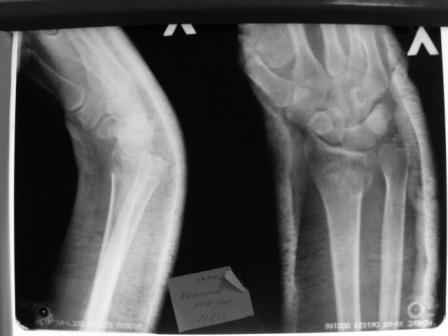

Уважаемые коллеги.Прошу обсудить случай лечения перелома дистального метаэпифиза лучевой кости. Ситуация скандальная и крайне неблагоприятная. Больная с патологической обстоятельностью мышления, склонностью к сутяжничеству, патологическими умозаключениями, не поддающимися коррекции (см. психиатрию, правда офиц. диагноза нет). В данном случае есть ряд ошибок с нашей стороны, прежде всего в отношении качества ведения документации (за что получил административное взыскание, по делом мне дураку). В остальном- придерживались в лечении подхода классический советской школы. Так как умную операцию…… сами знаете… 15.12- перелом луча в Москве. Там же репозиция, гипс. Дальнейшее лечение у нас в ЦРБ. 20.12.- вторичное смещение в гипсе21.12- под внутривенным наркозом- репозиция, гипсовая лонгета. Дальше начинается самое интересное. После репозиции больная заявила, что я (репозицию делал я) порвал ей все связки в суставе, посинел у нее 5 палец, якобы я за него тянул и т. д. На самом деле на 2 сутки после репозиции рука немного отекла и было незначительное сдавление гипсом, который был ослаблен. Дальнейшее лечение консервативное. Через 6 недель- гипс снят, назначено ЛФК. Пациентка крайне недовольна. Говорит, что на снимке у нее выступает кость, я ей сломал руку и.т.д. В общем началось. Пациентка прочитала в интернете наверное все, что есть по данной травме.По заключениями рентгенологов и консультанта из КДЦ областной больницы - стояние отломков допустимое. Объективно говоря- снижена высота лучевой кости, диастаз лучелоктевого сочленения, и не сросся шиловидный отросток. однако на РКТ при сравнении с другой стороной- разница незначительная. Дальше в одной из больниц нашей области и одной из больниц Москвы (вроде бы КГБ 53) врачи сказали, что репозиция сделана плохо. Нужна операция (восстановить длину лучевой кости), даже один из них предложил РЕДРЕССАЦИЮ (хи-хи) с наложением аппарата Илизарова. Что это для данной больной- радость неописанная. (см. описание психического статуса). Ничем другим, кроме зарабатывания дешевого авторитета объяснить данный факт не могу.Кстати, у больной еще нейропатия локтевого нерва.Для разрешения конфликта больная направлена на консультацию в ЦИТО на 03.03.11.

1. РЕПОЗИЦИЯ сделана качественно(ОСНОВНЫЕ 2 УГЛА ВЫСТАВЛЕНЫ ПРАВИЛЬНО ) , но перелом нестабильный и склонен к втор смещению . Поэтому мы стараемся все переломы со смещением фиксировать 3-МЯ спицами по GRIN методике .

2. По сравнению и без ! втор смещение незначительное.НЕТ НИКАКОЙ ,,локтевой косорукости,,маделунгов . но имеется смещение совести у врачей КГБ 35--НЕТ ЗДОРОВЫХ, есть только недообследованные ! Этому смещению аппарат внешней фиксации не поможет .Психопаткам в менопаузе да весной только этого и надо чуть толкнули и поехало .

1. Репозиция от 21.12.10 была выполнена лучше, чем первичная.

2. Укорочение лучевой кости с изменениями дистального лучелоктевого сустава требует оперативного лечения